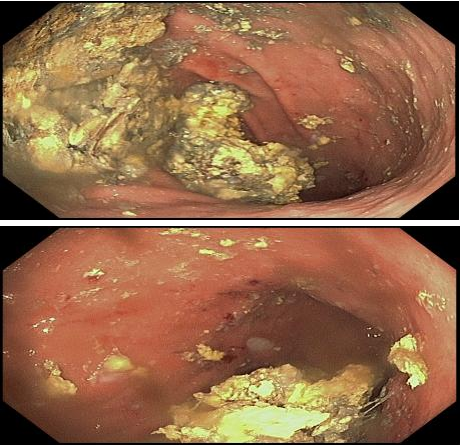

患者周女士(化名)因腹胀、上腹疼痛、呕吐咖啡样物来院就诊。胃镜检查发现胃腔内有三枚巨大结石,最大约500px×250px,严重影响胃功能,若不处理,极易引发出血、梗阻或穿孔。传统开腹手术创伤大、恢复慢,经评估后,内镜诊疗中心团队决定采用经内镜胃石体内碎石术。

在麻醉医生配合下,患者全程舒适无痛。李洪平主任通过口腔送入纤细内镜,利用钬激光碎石器精准击碎结石,并配合电圈套器分割、取出。经过细致操作,巨石被成功粉碎成细小碎块,部分取出,其余随肠道自然排出。手术过程顺利,患者术后无切口、无明显疼痛,腹胀症状迅速缓解。